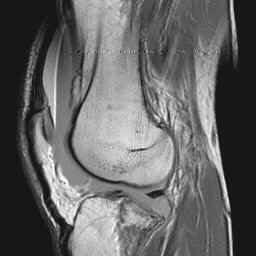

CASE 1: These three MRI images are from the 50 year old male who fell 1 day prior to presentation and whose radiographs are displayed on the KNEE RADIOGRAPHY page.

Image 2: Sagittal proton density image at the same level. CLICK TO ENLARGE.